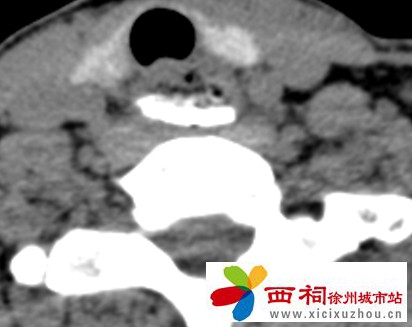

接诊后,沛县人民医院立即开启绿色通道。耳鼻喉科医生第一时间为患者安排相关检查,影像结果显示:食管上段异物滞留,伴有穿孔风险!若发生食管穿孔,可能引发严重感染,直接威胁患者生命,情况十分危急。

微信图片_2025-10-14_144235_630.jpg

评估病情后,耳鼻喉科迅速发起多学科会诊,会诊由医院院长蔡建平亲自主持,并与正在休假的消化医学中心主任、帮扶专家符强进行线上会诊支持。经团队充分讨论,最终确定了行内镜下食管异物取出术的治疗方案。